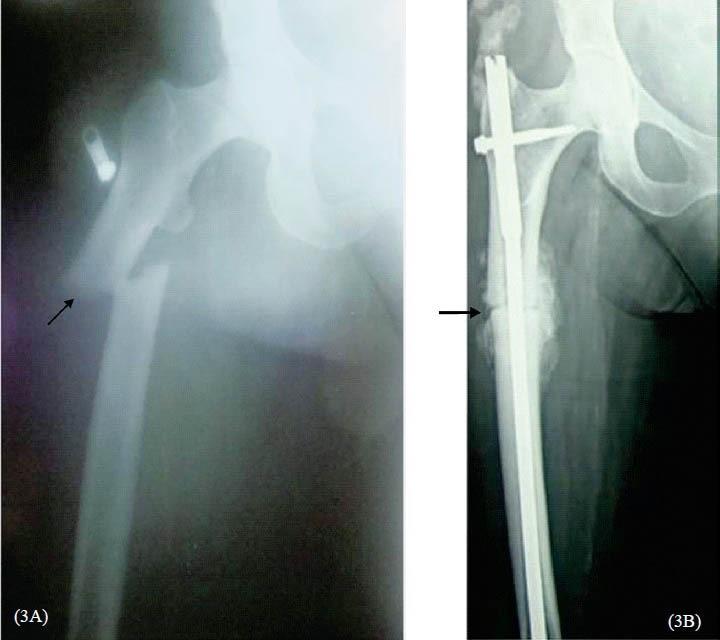

Of the eight patients, who sustained atypical femoral fractures, six were on alendronate and two were on zoledronate therapy before the fractures. In addition to BPs, two patients were on long term corticosteroid therapy for rheumatoid arthritis and Addison's disease. Three patients had bilateral atypical femoral fractures. Except one, all of them had prodromal symptoms prior to fracture. Skeletal radiograph showed cortical thickening, pointed (beaking of) cortical margin and transverse fracture in meta-diaphyseal location. Serum calcium, phosphate, alkaline phosphatase (ALP) and intact parathyroid hormone (iPTH) concentrations were within the reference range in all patients.

在8例发生非典型股骨骨折的患者中,6例在骨折前接受阿仑膦酸盐治疗,2例接受唑来膦酸盐治疗。除双膦酸盐外,2例患者因类风湿性关节炎和艾迪生病接受长期皮质类固醇治疗。3例患者发生双侧非典型股骨骨折。除1例患者外,所有患者在骨折前均有前驱症状。骨骼X线检查显示皮质增厚、皮质边缘尖(喙状)和干骺端横形骨折。所有患者的血清钙、磷、碱性磷酸酶(ALP)和完整甲状旁腺激素(iPTH)浓度均在参考范围内。